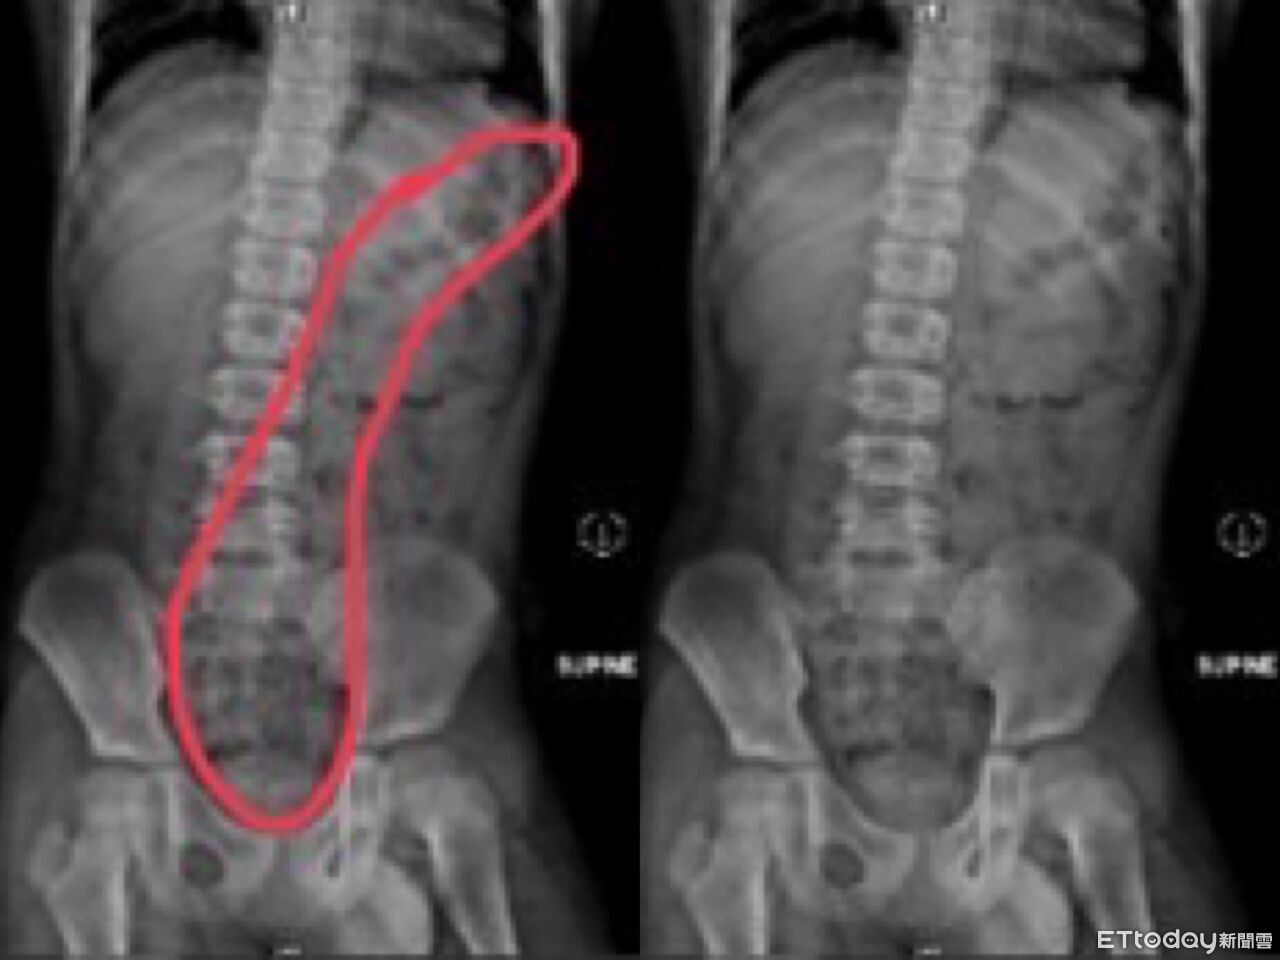

近日,高雄一名11歲男童因腹痛、冒冷汗、嘴唇發紫及手腳冰冷等症狀被緊急送往急診。經過醫師診斷,發現男童腹部X光檢查結果顯示腹內積滿糞便,確診為嚴重便秘。男童母親表示,孩子平時習慣邊玩手機邊上廁所,經常因被催促而匆忙結束,導致無法確定是否排便完全。

高雄一名11歲男童因腹痛、冒冷汗、嘴唇發紫被送到急診,經醫師診斷為便秘,經灌腸後解出一堆大便,男童母親表示,孩子喜歡上廁所滑手機,每次被臭罵才離開廁所。醫師提醒,便秘不是一兩天造成的,長期便秘會導致食慾不佳,嚴重可能造成生長遲滯,需要透過藥物治療並調整生活、飲食習慣。